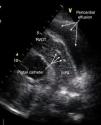

A 77-year-old woman presented to our emergency department with worsening shortness of breath. She was hemodynamically stable. Initial work-up was significant for hemoglobin 10.3 g/dl and enlarged cardiac silhouette on the chest X-ray. Transthoracic echocardiography showed a large circumferential pericardial effusion and dilated inferior vena cava. There was no right chamber collapse. Therapeutic pericardiocentesis was performed in the cardiac catheterization laboratory. An attempt was made to drain the pericardial fluid through a subxiphoid window under fluoroscopic guidance using a percutaneous needle. About 200 ml of serosanguinous fluid was aspirated. A guide wire was then advanced through the needle hub, the needle was removed and a pigtail catheter was introduced and left in place through a catheter-over-wire technique for further drainage. The procedure was considered successful by the performing cardiologist and the patient was admitted. No further drainage was noticed during the next 12 hours. The patient remained stable but did not report any improvement in her symptoms. Follow-up echocardiography 12 hours after the procedure showed massive pericardial effusion with dilated inferior vena cava. The catheter was seen in the right ventricle passing through the right ventricular free wall (Figures 1 and 2). Intravenous injection of agitated saline showed the catheter had advanced to the main pulmonary artery (Figure 3, Videos 1-3). Inadvertent right ventricular perforation and advancement of the pigtail catheter to the pulmonary artery was diagnosed and the patient required surgery for removal of the catheter and repair of the right ventricular free wall.